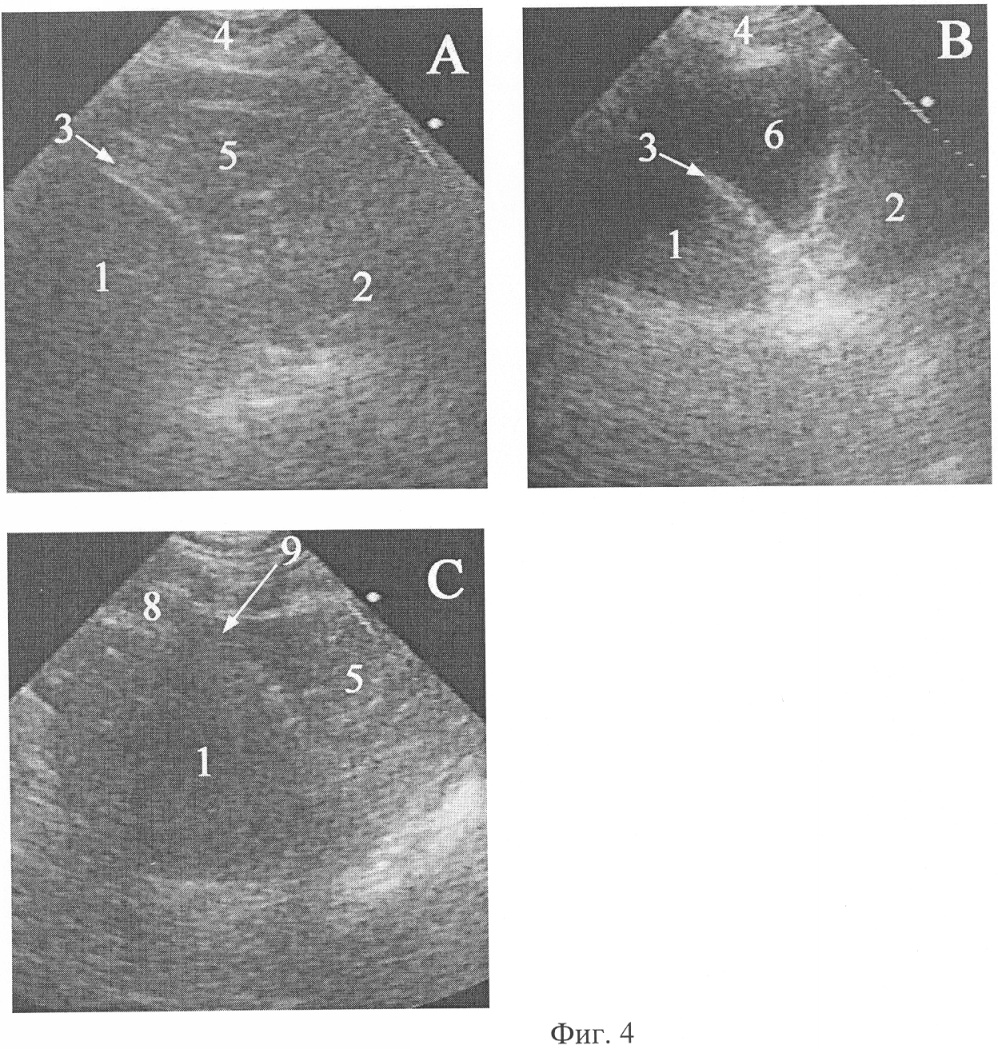

Фиг.4. Эхограммы абдоминомедиастинальной липомы больной М. и целомической кисты перикарда больной С. (рисунок к клиническому примеру 1).

На фиг.4 и 5 обозначено:

А – поперечное сканирование абдоминомедиастинальной липомы из-под мечевидного отростка с направлением оси сканирования к правому плечу, В – поперечное сканирование целомической кисты перикарда из-под мечевидного отростка с направлением оси сканирования к правому плечу, С – продольное сканирование сообщения абдоминомедиастинальной липомы с предбрюшинной жировой клетчаткой,

1 – печень, 2 – сердце (лоцируется нечетко из-за движения), 3 – медиальная поверхность правого купола диафрагмы, 4 – мягкие ткани грудной стенки, 5 – абдоминомедиастинальная липома, 6 – целомическая киста перикарда, 7 – капсула целомической кисты перикарда, 8 – предбрюшинная жировая клетчатка, 9 – связь абдоминомедиастинальной липомы с предбрюшинной жировой клетчаткой.